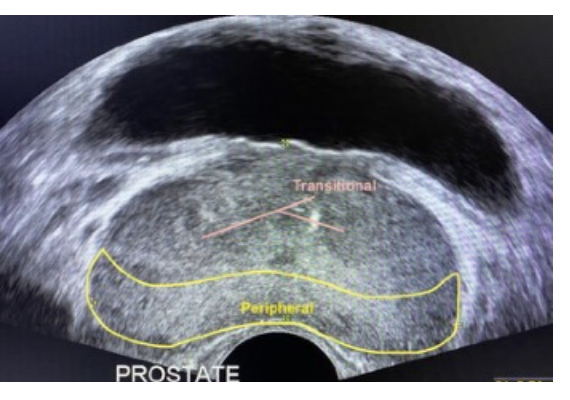

Which prostate zone is the largest?

Peripheral zone.

Where is the peripheral zone located?

Posterior and apical region of the prostate.

Which prostate zone is at the base (superior)?

Central zone.

Which prostate zone surrounds the urethra?

Transitional zone.

What is the anterior fibromuscular stroma?

In the coronal plane, which prostate zone is closest to the transducer footprint?

Peripheral zone (also apical)